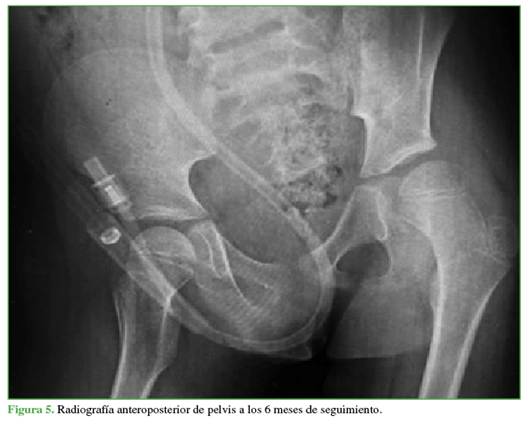

En las radiografías de control a los 3 (Figura 4) y 6 meses (Figura 5), no se visualizaron hallazgos de NAV y también se descartaron otras complicaciones osteomusculares asociadas a la luxación traumática.

Las radiografías de control no mostraron signos sugestivos de NAV (esclerosis, colapso, quistes, reducción del espacio articular, etc.).22 Estos hallazgos pueden demorar de 2 a 6 meses en hacerse visibles en las radiografías,20 por lo que la temporalidad del seguimiento fue adecuada.

A pesar de la ausencia de hallazgos radiológicos de NAV hasta los 6 meses, es necesario continuar con un protocolo de seguimiento con estudios por imágenes en búsqueda de signos de desarrollo de NAV, que pueden demorar hasta 2 años en manifestarse.25